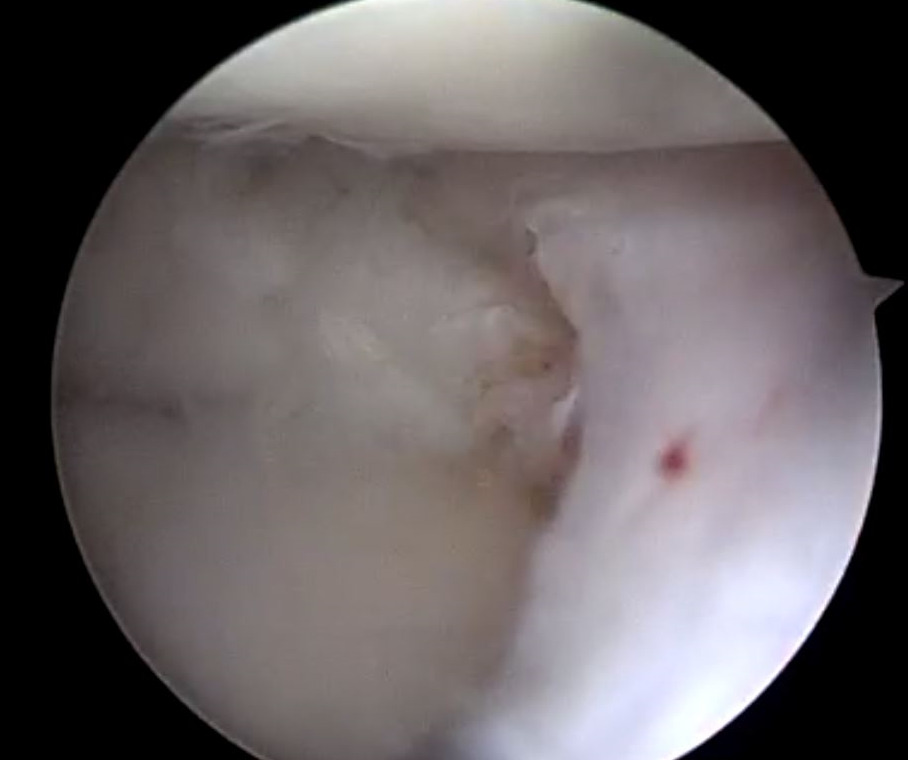

Saucerization of the redundant lateral meniscal tissue aided in the reduction of the displaced meniscus (Figure 9).

Discoid meniscus morphology contributes to a predisposition for meniscal tears. Homogenous collagen fiber organization is lost within the discoid morphology, with the periphery of the discoid meniscus maintaining a typical uniform parallel fiber orientation and the central portion having a more random fiber orientation (Bisicchia, Botti, and Tudisco 2018; Atay et al. 2007; Kim, Han, and Lee 2016). This demarcation of tissue organization was appreciated arthroscopically and used to determine level of saucerization (Figure 10). The unique histological structure likely leads to inability to resist forces while dissipating hoop stresses within the knee joint, resulting in increased tear rates with minimal trauma.